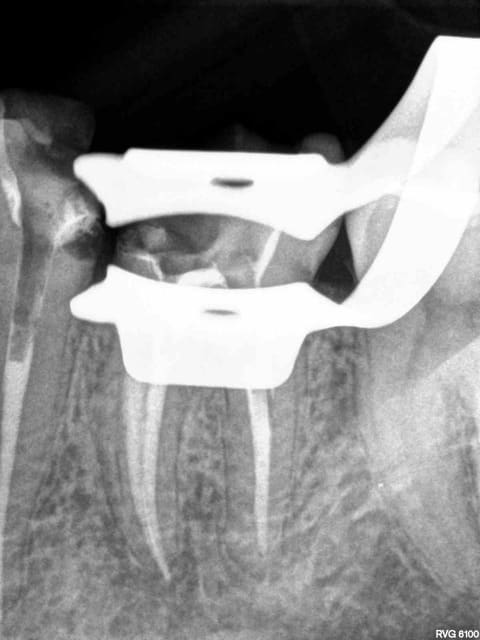

Cas d'école : compos sur 35, 36 2 ans, et endo 35 36 hier.

Surtout pas en faire état tu as raison que ca continue comme ca !

PS : manque une étape, l'endo-peinture canalaire- coiffe, on a perdu des parts de marché sur ce coup là !-)))))